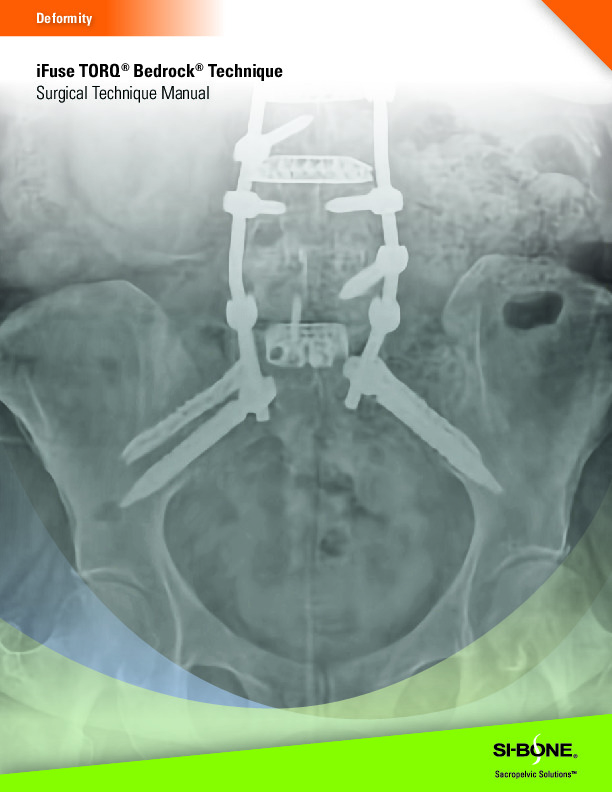

The iFuse TORQ by SI-Bone is a 3D printed titanium screw for use in the fusion and stabilization of the sacroiliac joint. It features a porous open architecture utilizing FuSIon 3D Surface Printed Porous Lattice which allows for osseous integration.

• 3D printed open porous architecture for osseous integration

• Helical Flutes with fenestrations for self-harvesting of autograft

• EZDrive Tip with self drilling and self tapping